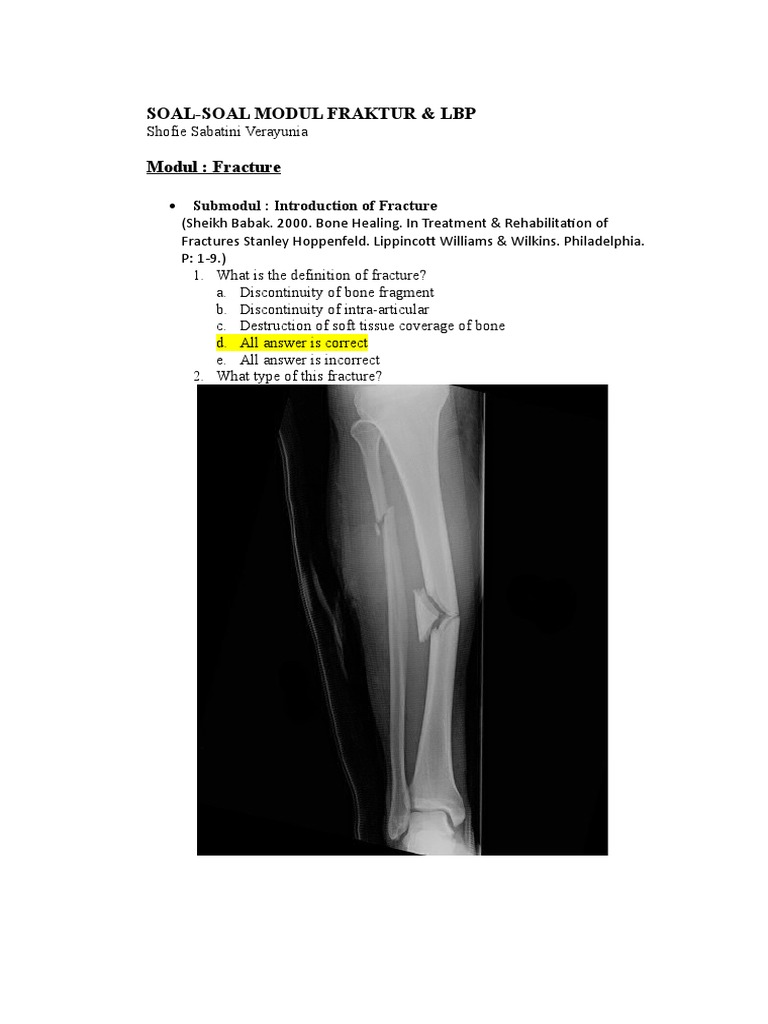

2